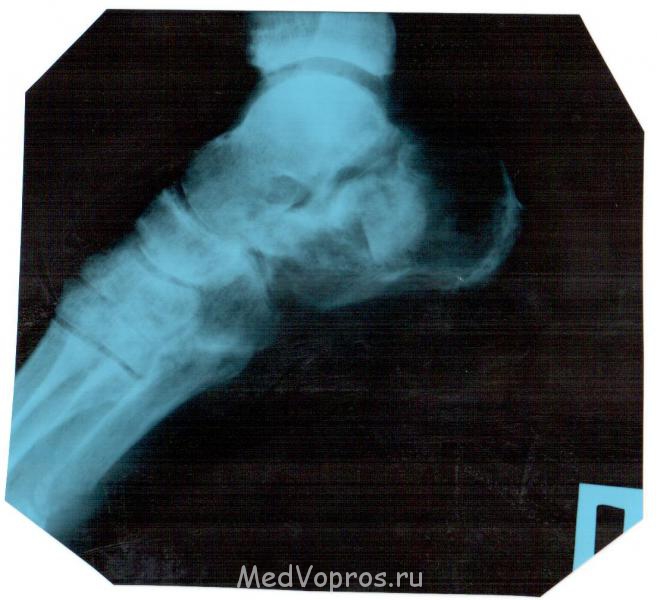

8 августа 2011г упал со стремянки результат оскольчатый перелом пяточной кости. раскажите как проходит заживление. наш хирург не чего не говорит. сказал три месяца лангеты и всё. самочуствие ноги. когда опускаю она стаёт красно фиолетовая бегают по ней мурашки отикает к вечеру жгёт в районе перелома дёргает как током бьёт. сколько времени на реабилитацию снимок 12 недель 4 месяц хожу на одной локтевом костыле

Перелом пяточной кости